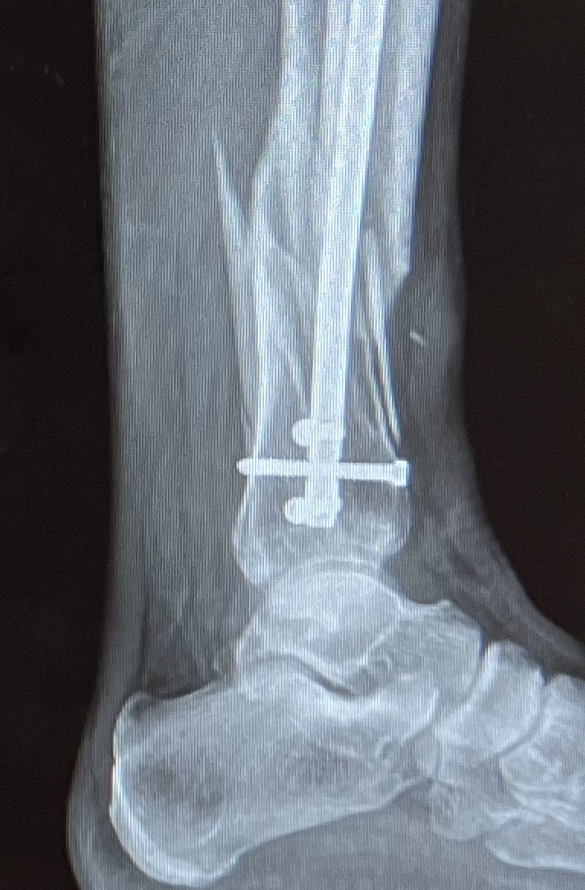

Op mijn werk (op een gesloten opnameafdeling van een psychiatrisch ziekenhuis) sloeg een agressieve jongeman mij een keer of tien tegen mijn gezicht en hoofd. Het bloed zat overal. Ik zakte bewusteloos in elkaar en brak mijn onderbeen op een bijzonder nare manier. De breuk leek op mij: open doch gecompliceerd, met weinig structuur en wat scherpe kantjes. Ik kreeg een infectie en lag weken in een ziekenhuis met om mijn been een stalen constructie. De breuk groeide verkeerd vast, dus kreeg ik een half jaar later een herstel operatie. Dat dit alles geen pretje was, is een understatement. Sterker nog: als je zegt dat ik een slechte tijd heb gehad, is dat nog steeds een understatement. Het was verschrikkelijk. Toch was het niet onoverkomelijk. Alles doet het nog (of weer) en als dat niet zo was geweest, heb ik ervaren, zou het leven ook gewoon zijn doorgegaan.